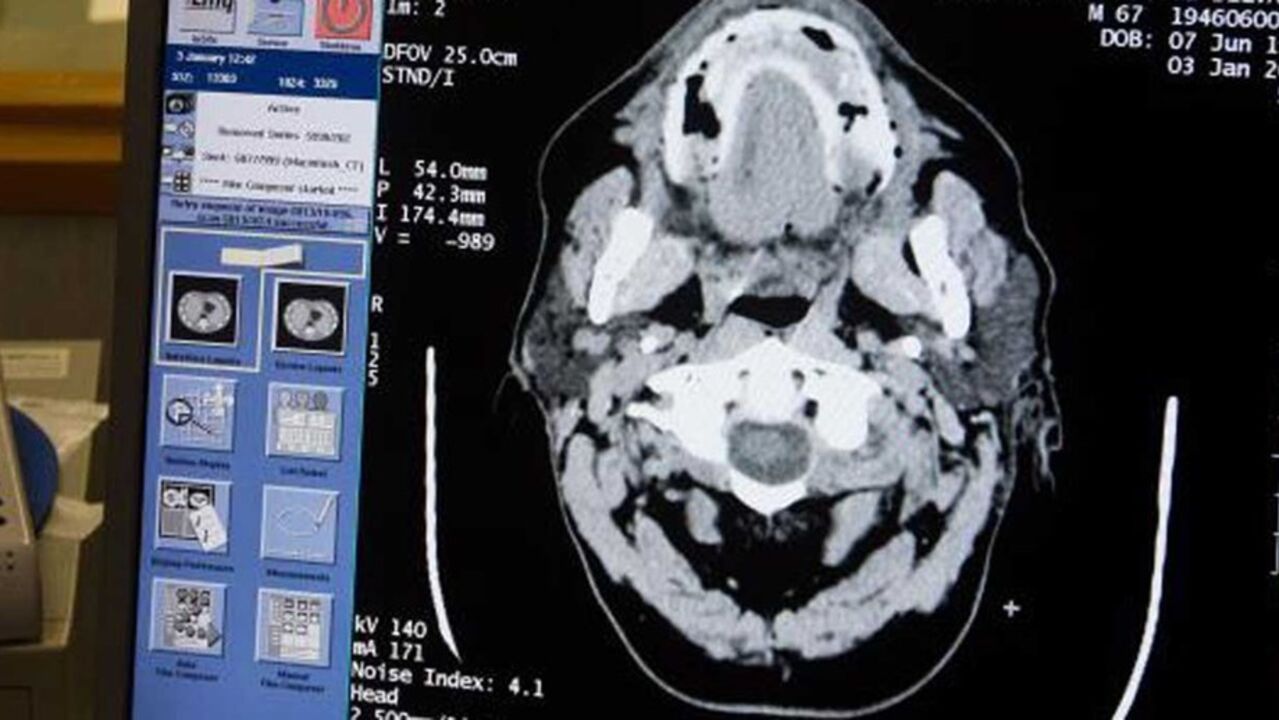

Bobby Charlton sofre da doença que já tinha estado na origem da morte de Nobby Stiles

A notícia divulgada pelo Manchester United de que ‘Sir’ Bobby Charlton sofre de demência abalou o mundo do futebol. Uma das maiores figuras da história do desporto britânico, o antigo jogador, de 83 anos, pertenceu à geração de ouro do futebol inglês que se sagrou campeã do mundo em 1966.